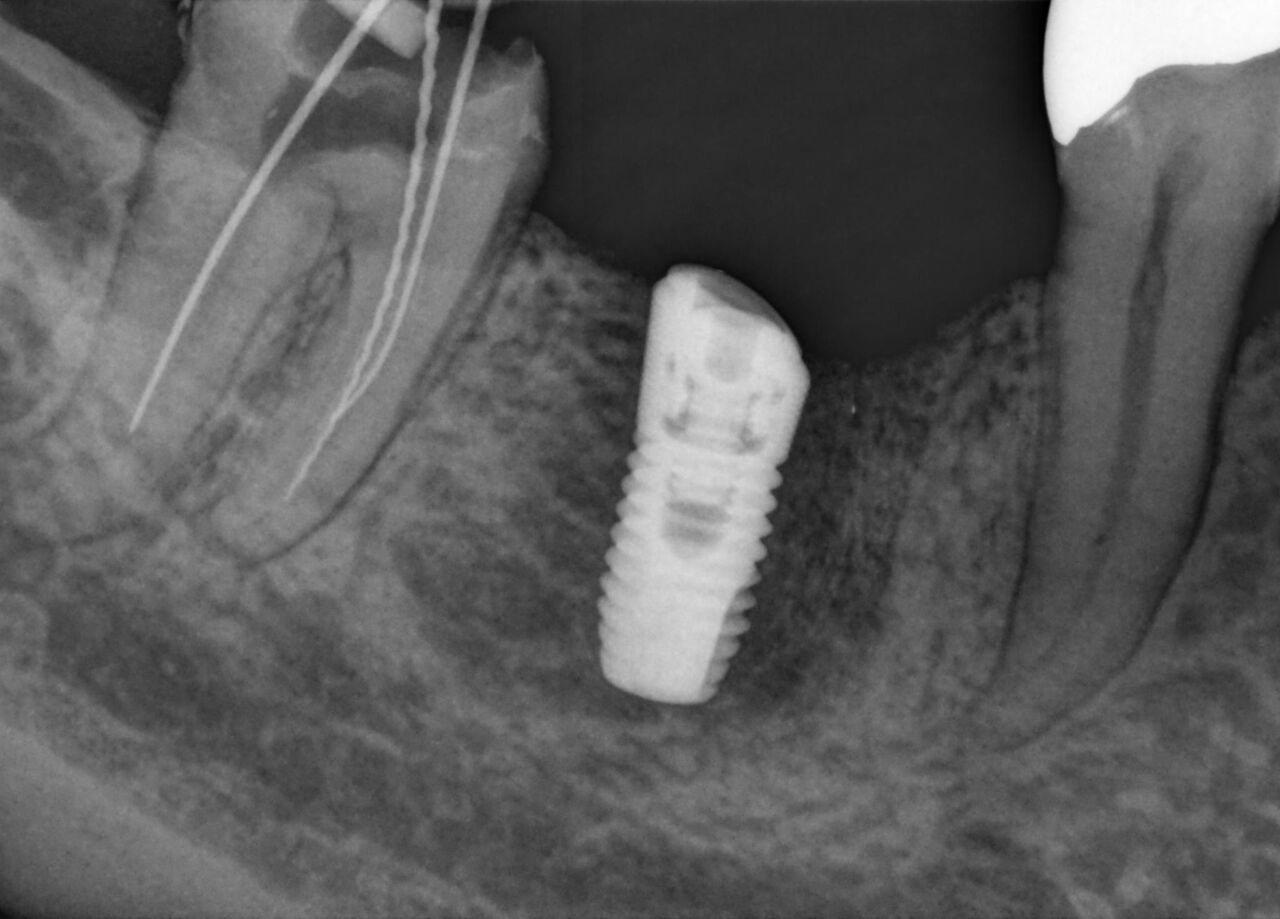

Schick AE sensors support a high clinical performance level with superior image quality and advanced filtering enhancements to highlight relevant anatomical structures and facilitate an accurate and detailed diagnosis. Low-noise images, improved visibility of details and dedicated filtering in indications such as endodontic cases or tooth decay, provide a relevant advantage in diagnostic certainty and help aid true confidence in the treatment assessment. When combined with smart connectivity between the hardware and Sidexis 4 software, you get the perfect partner for any practice.

Schick AE has a theoretical resolution of 33 lp/mm and a 15 μm pixel size. In combination with dedicated filters and the enhanced dynamic range you get superior X-rays to support your diagnosis.

Increased sensor sensitivity and an enhanced low-dose optimized exposure spectrum allow for optimal visibility and diagnostics at reduced exposure. Underexposed images are successfully counterbalanced, granting consistent image quality and dose flexibility.